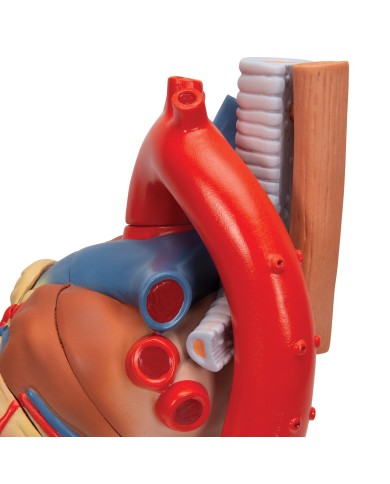

Modello anatomico di cuore, ingrandito 2 volte, su cavalletto

Questo modello dettagliato mostra, oltre alle strutture anatomiche del cuore, anche una parte del diaframma (base)

Realizzato in stampa 3D ad elevatissima risoluzione a colori.

Realizzato in stampa 3D ad elevatissima risoluzione a colori.

Realizzato in stampa 3D ad elevatissima risoluzione a colori.